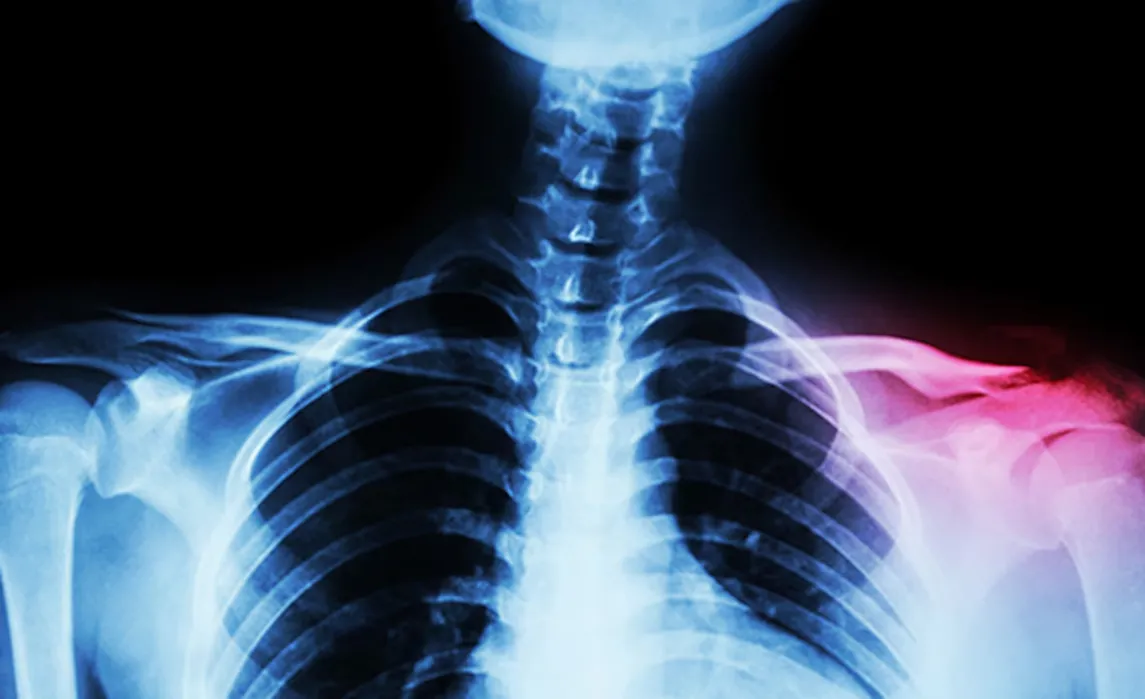

Una fractura de clavícula se diagnostica mediante un examen físico y radiografías.

Por su parte, Medline Plus, un servicio de la Biblioteca Nacional de Medicina de Estados Unidos, explica que la clavícula es un hueso largo y delgado ubicado entre la parte superior del tórax (esternón) y el hombro. Su función principal es brindar soporte y estabilidad a esta articulación.